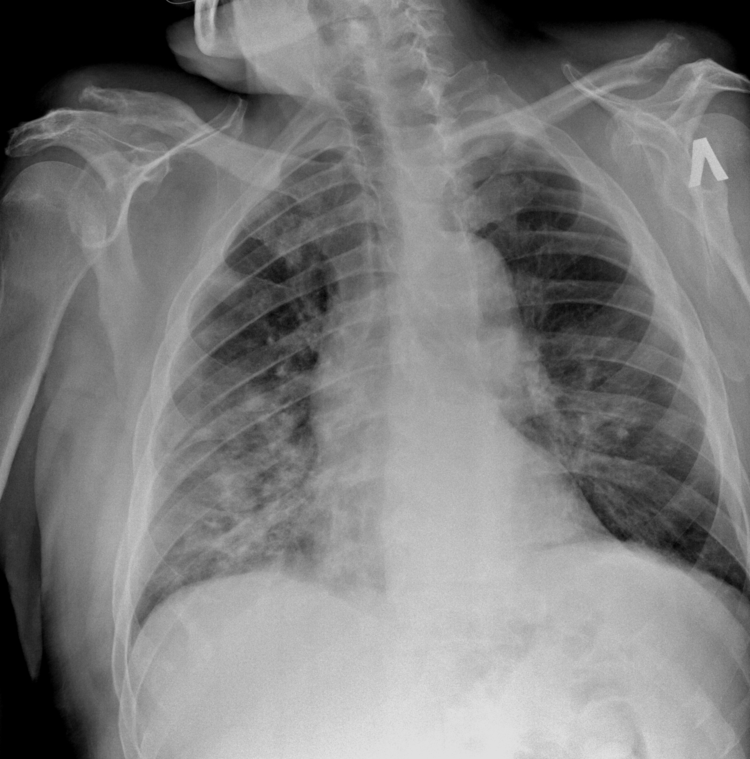

ИИ и алгоритмы интеллектуального анализа рентгеновских снимков грудной клетки. Выявление множества нарушений менее чем за 1 минуту